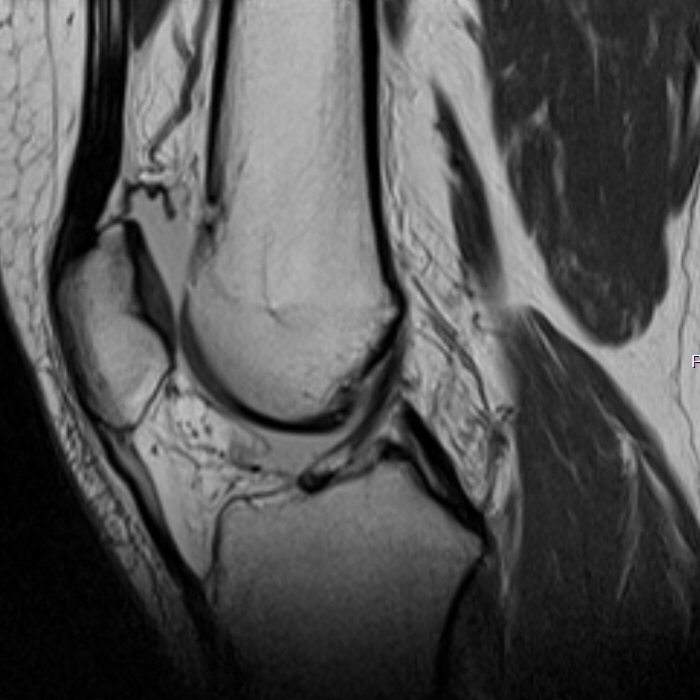

MR-bild som visar normalt främre korsband

MR-bilder som visar ruptur av främre korsbandet